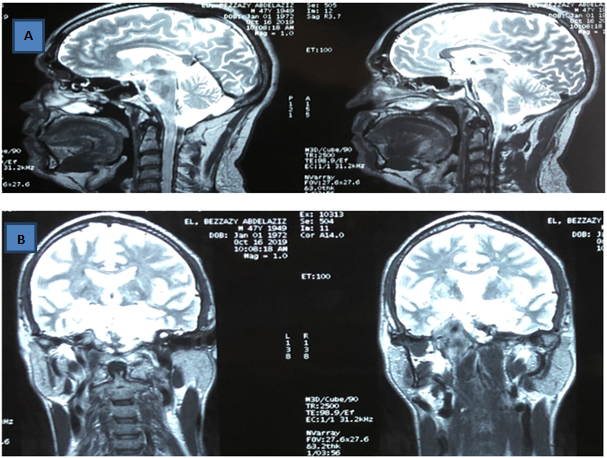

Orbito-cerebral MRI: in favor of a right nasopharyngeal neoplastic process, extended to the right cavernous compartment (Figure 4A,4B).

Figure 4A & 4B Orbito-cerebral MRI (coronal and sagittal slice) in favor of a right nasopharyngeal neoplastic process, extended to the right cavernous compartment.